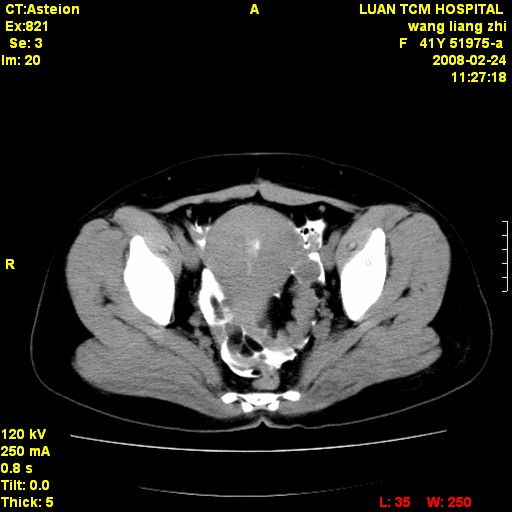

以下是引用dyqct在2009-8-23 16:17:00的发言:[br]考虑:1、造影剂进入腹腔、结肠旁沟、肝周;[br] 2、子宫明显增大(腺肌增生症?);[br] 3、膀胱显影是由于造影剂吸收后经肾分泌进入膀胱的;[br] 4、建议mri检查子宫。